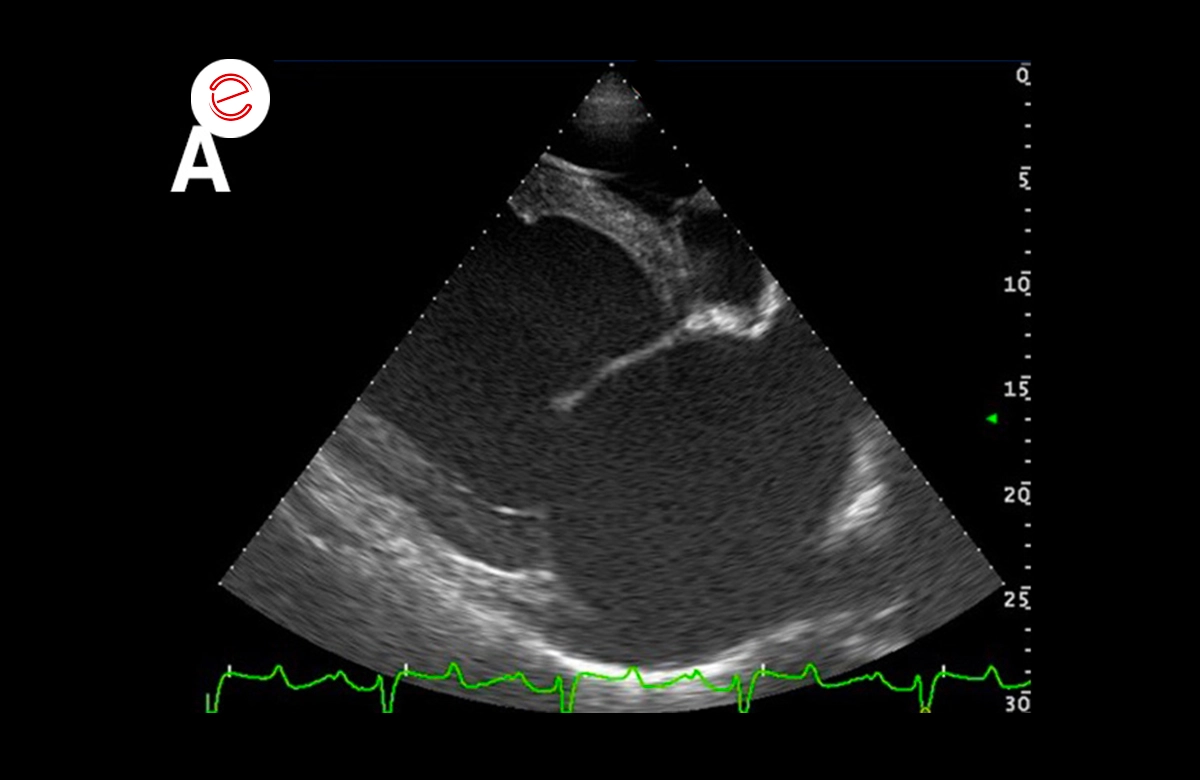

Right parasternal 4 chamber view (A) and left parasternal view of the left atrium and ventricle: significant dilation of the left atrium (v 166,4 mm; v.n 116 ± 7 mm) and the ventricle (systolic v 163.2 mm; v.n 112 ± 8 mm – diastolic v. 86.7) which present a globular aspect.

Right parasternal 4 chamber view (A) and left parasternal view of the left atrium and ventricle: significant dilation of the left atrium (v 166,4 mm; v.n 116 ± 7 mm) and the ventricle (systolic v 163.2 mm; v.n 112 ± 8 mm – diastolic v. 86.7) which present a globular aspect.